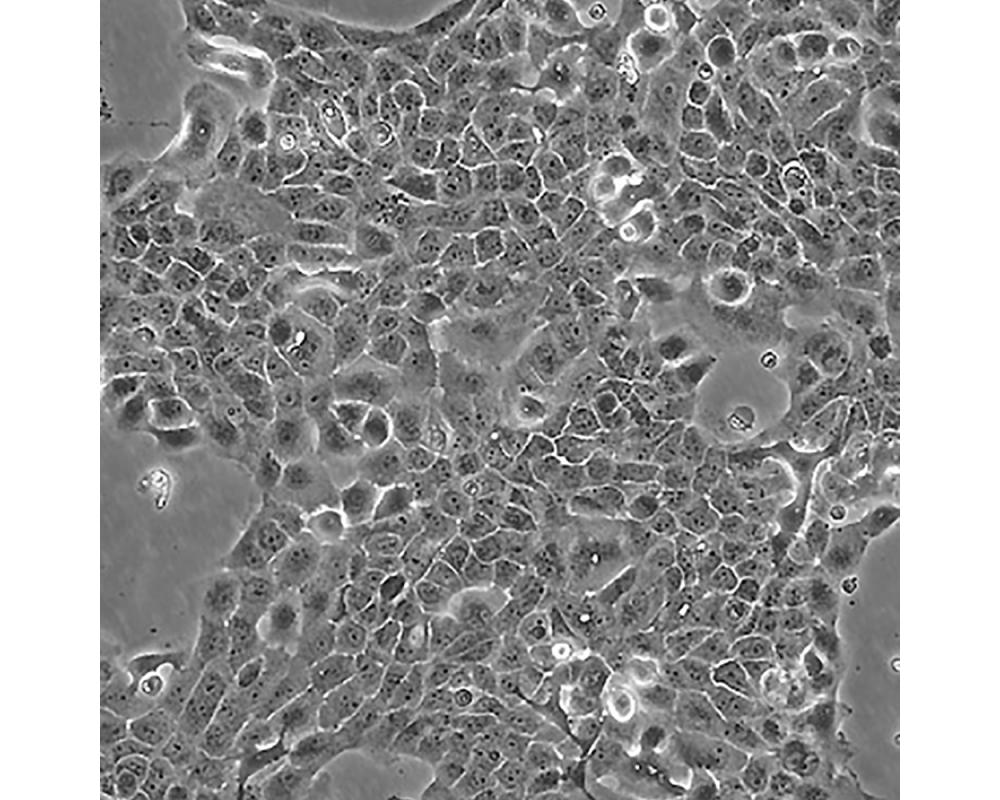

A-431(A431,A 431)

中文名稱 人皮膚鱗癌細胞

組織來源 外陰鱗狀細胞癌;女性

細胞種屬 Homo sapiens, human

生長特性 adherent

培養基 DMEM+10% FBS+1% P/S

形態特征 epithelial

細胞描述 該細胞源自一位患有皮膚鱗狀細胞癌的85歲女性,是GiardDJ等人建立的一系列細胞株中的一株。該細胞在免疫抑制小鼠體內可成瘤,在瓊脂上培養可形成克??;是一個超三倍體人細胞株。